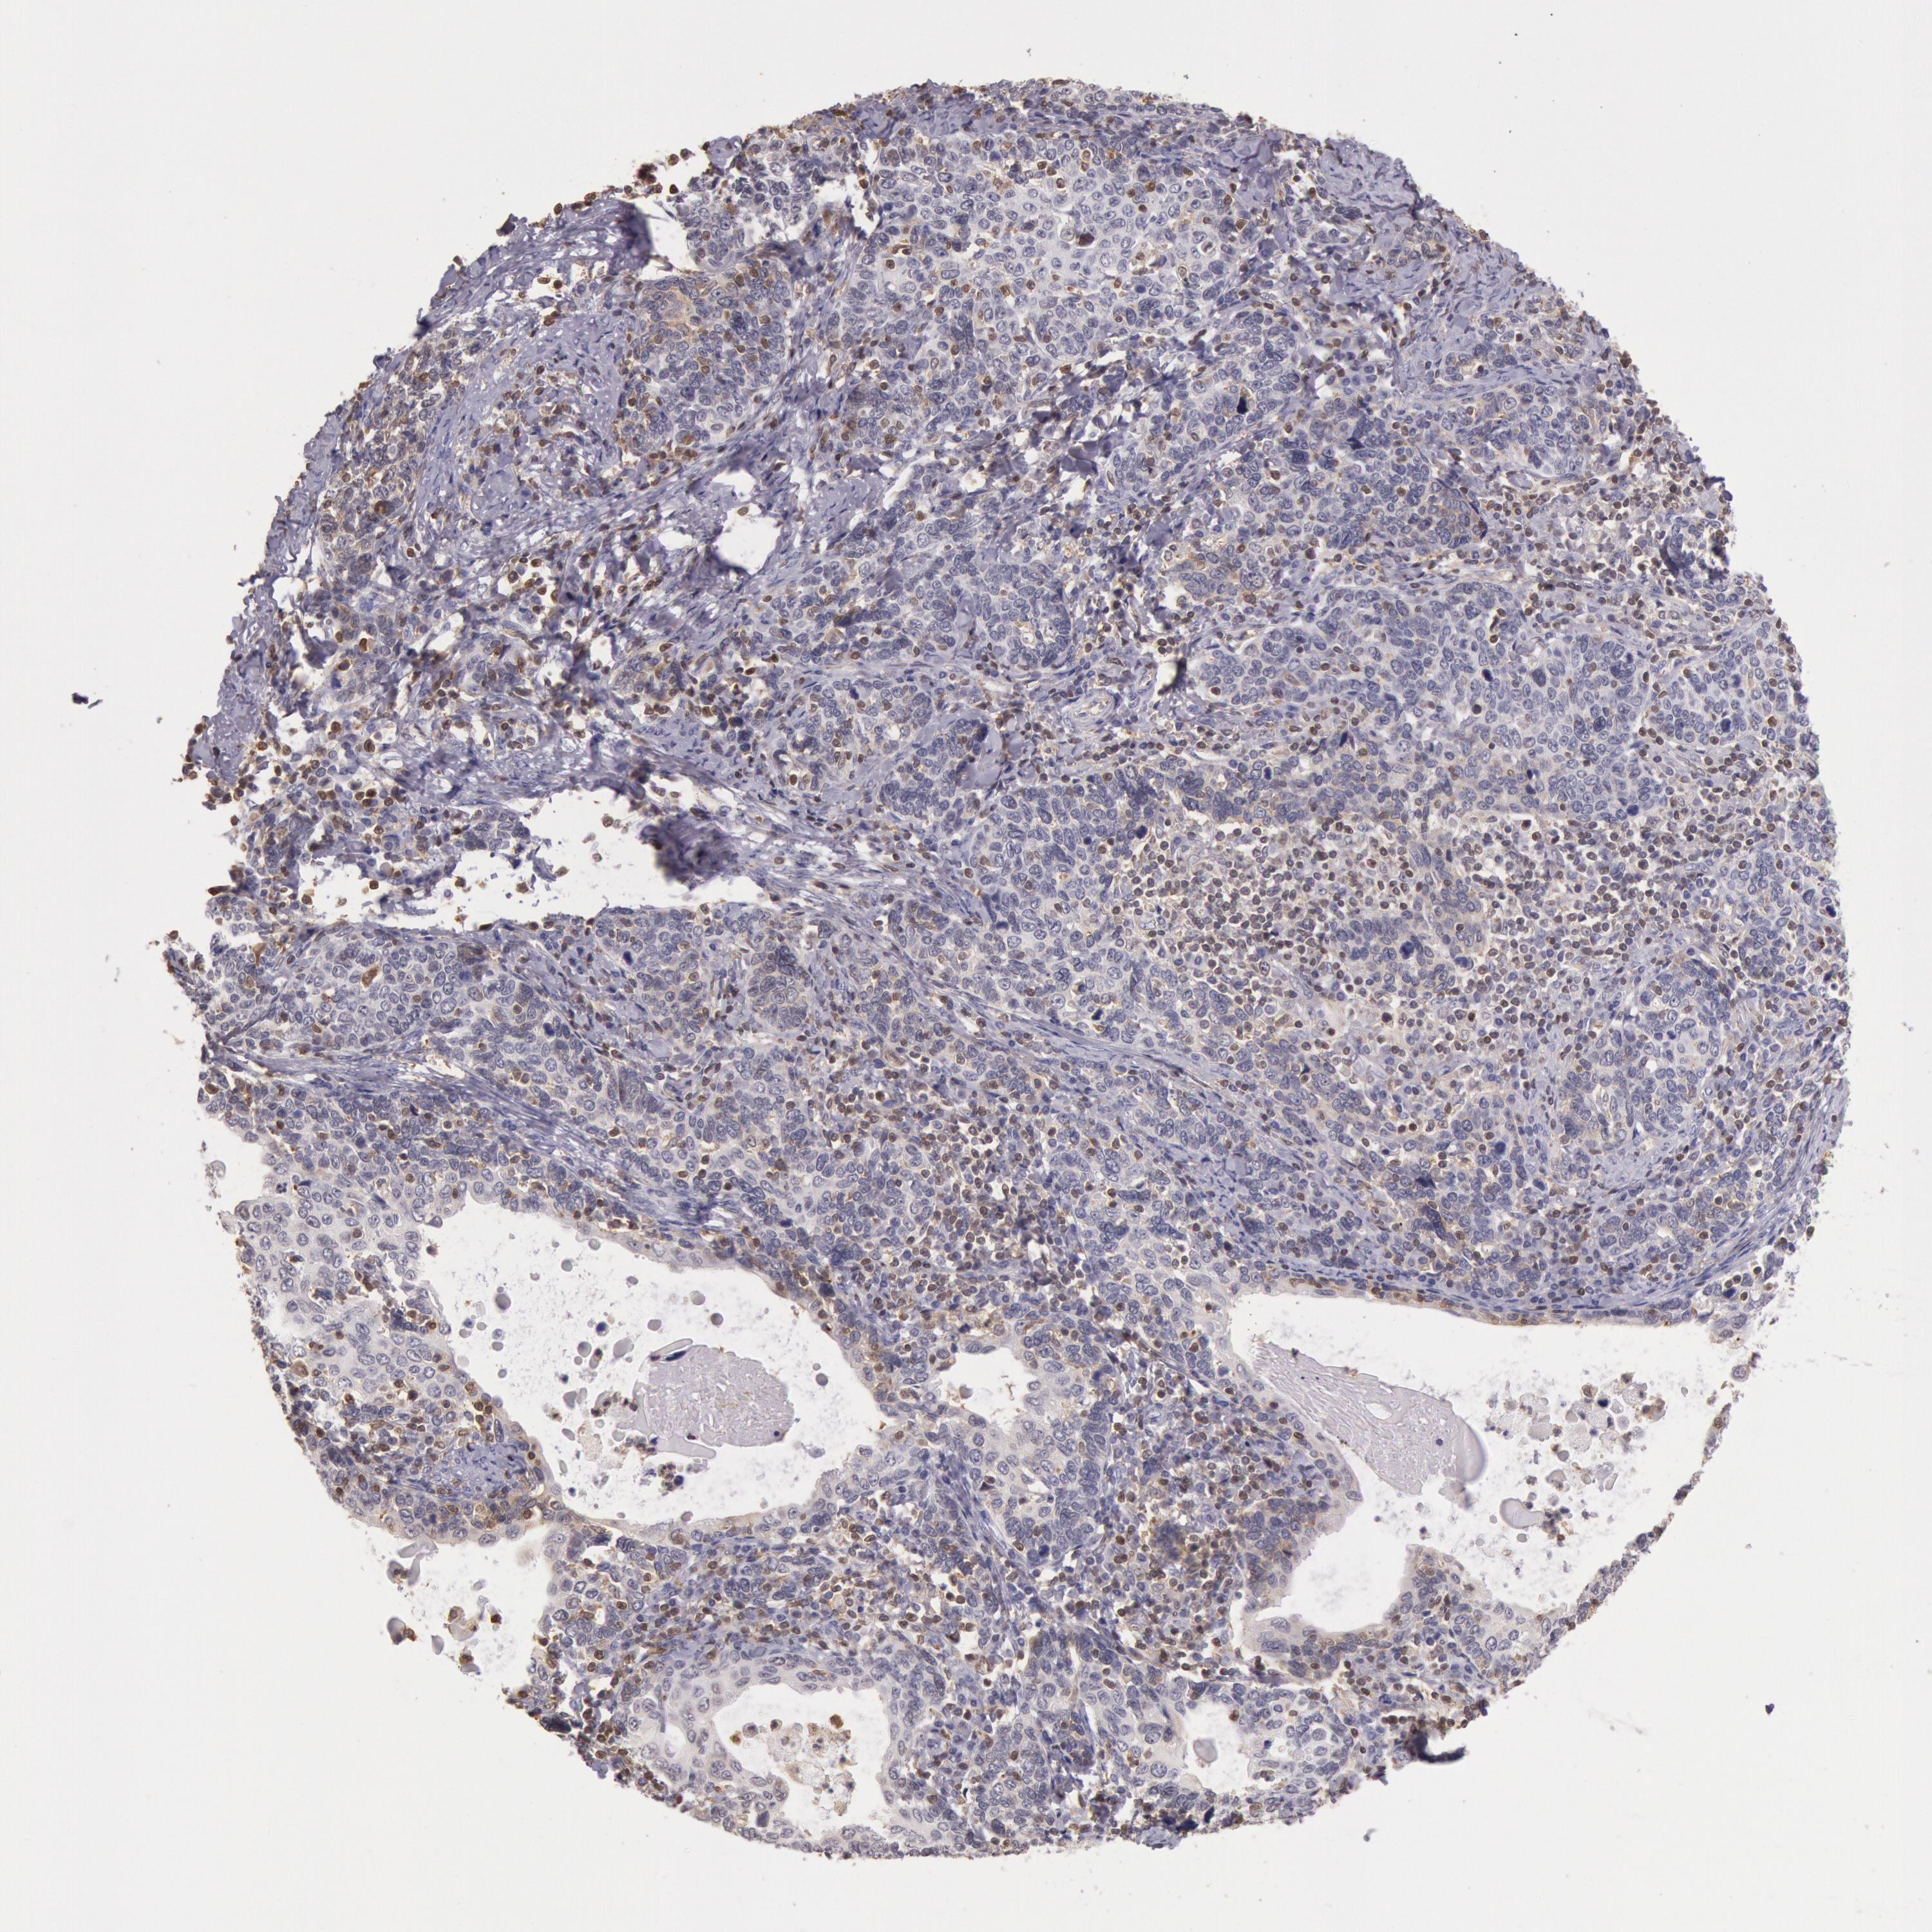

CERVICAL CANCER - Protein expressioni

A mouse-over function shows sample information and annotation data. Click on an image to view it in a full screen mode. Samples can be filtered based on level of antibody staining by selecting one or several of the following categories: high, medium, low and not detected. The assay and annotation is described here.

Note that samples used for immunohistochemistry by the Human Protein Atlas do not correspond to samples in the TCGA dataset.

Antibody stainingi

Antibody staining in the annotated cell types in the current human tissue is reported as not detected, low, medium, or high, based on conventional immunohistochemistry profiling in selected tissues. This score is based on the combination of the staining intensity and fraction of stained cells.

Each image is clickable and will lead to virtual microscopy that enables deeper exploration of all samples and also displays staining intensity scores, fraction scores and subcellular localization as well as patient and tissue information for each sample.

Antibody HPA001275

Antibody CAB017442

Staining

High

Medium

Low

Not detected

Intensity

Strong

Moderate

Weak

Negative

Quantity

>75%

75%-25%

<25%

None

Location

Nuclear

Cytoplasmic/membranous

Cytoplasmic/membranous,nuclear

Squamous cell carcinoma, NOS